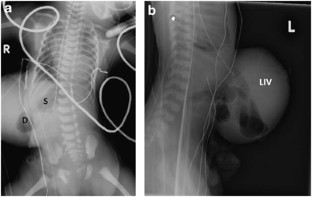

Herman, T., Siegel, M. Giant omphalocele, intrinsic duodenal obstruction. J Perinatol 31, 293–295 (2011). https://doi.org/10.1038/jp.2010.163